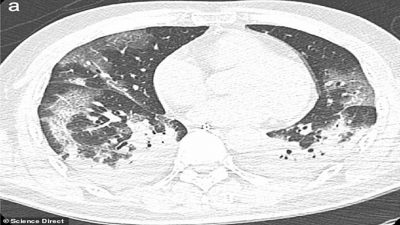

Los especialistas del Instituto Nacional de Enfermedades Infecciosas en Roma estudiaron los cuerpos de los pacientes de 65 y 67 años y detectaron, mediante rayos-X y tomografías computarizadas, un gran deterioro en la función de los pulmones.

Cuando coronavirus ataca los pulmones, provoca una inflamación en las membranas mucosas, lo genera un daño en los alvéolos pulmonares, que tienen que trabajar más para suministrar oxígeno a la sangre que circula por todo el cuerpo y eliminar el dióxido de carbono para que se pueda exhalar. La inflamación y el daño al flujo de oxígeno pueden causar que dichas áreas en los pulmones se llenen de fluido, pus y células muertas.